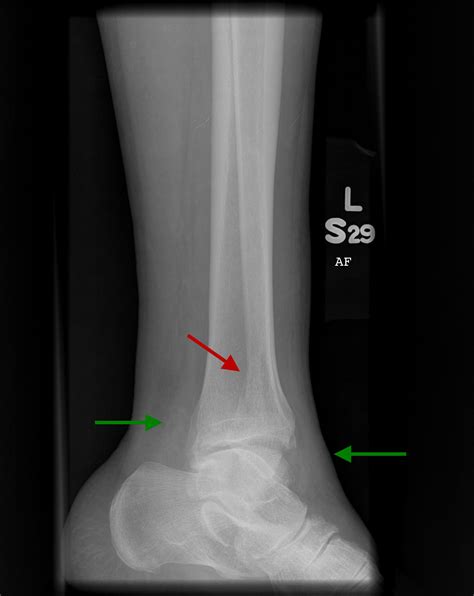

Suffering a fracture can be a daunting experience, and the most common question patients ask their orthopedic surgeons is regarding the expected broken ankle recovery time. Healing is not a one-size-fits-all process; it is a complex journey influenced by the severity of the break, your overall health, and how diligently you adhere to your rehabilitation plan. Understanding the timeline of recovery can help manage expectations and ensure that you are taking the right steps toward regaining mobility and strength.

• Severity of the Fracture: A hairline or simple fracture will heal much faster than a complex, comminuted fracture involving multiple bones or displaced fragments that require surgical intervention.

• Surgical Intervention: If your injury required hardware—such as plates, screws, or rods—to stabilize the bone, your recovery process will include extra time for soft tissue healing around the surgical site.